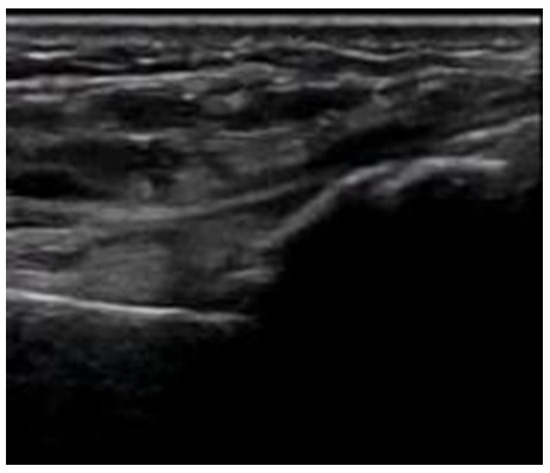

- Use of color and power Doppler: When employing Doppler techniques to assess vascularity related to inflammation or healing, care must be taken to avoid excessive probe pressure. Over compression of the tissue can collapse small vessels, leading to false-negative findings.